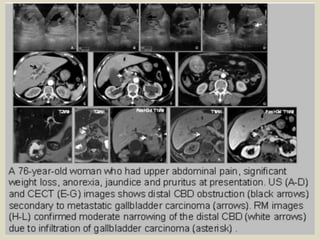

Carcinoma of gallbladder Irregular mass at the gallbladder

fundus with peri-hilar lymph nodes compression.

Carcinoma of gallbladder with biliary compression by metastatic lymph nodes A 52 years

old woman presented with obstructive jaundice. (a,b) CT image revealed lymph nodal mass

at the porta hepatis (arrow) with intrahepatic biliary ducts dilatation. (c) The CBD is not

dilated in its distal portion. (d)A gallbladder focal lesion highly enhanced at the fundus.

Tumoral invasion of the bile ducts Most extrinsic tumors displace

the biliary tree, or occasionally will encircle it, narrowing the duct

lumen and causing obstruction. The classic tumor narrowing the

bile duct in this way is pancreatic carcinoma. Extension of

gallbladder carcinoma through the hepatic hilum can entrap and

narrow the bile duct. Other less common tumors with extension